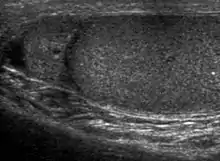

Sonography of a normal testis. The normal testis presents as a structure having homogeneous, medium level, granular echotexture. The mediastinum testis appears as the

hyperechoic region located at the periphery of the testis as seen in this figure. | |

The normal adult testis is an ovoid structure measuring 3 cm in anterior-posterior dimension, 2–4 cm in width, and 3–5 cm in length. The weight of each testis normally ranges from 12.5 to 19 g. Both the sizes and weights of the testes normally decrease with age. At ultrasound, the normal testis has a homogeneous, medium-level, granular echotexture. The testicle is surrounded by a dense white fibrous capsule, the tunica albuginea, which is often not visualized in the absence of intrascrotal fluid. However, the tunica is often seen as an echogenic structure where it invaginates into the testis to form the mediastinum testis. In the testis, the seminiferous tubules converge to form the rete testes, which is located in the mediastinum testis. The rete testis connects to the epididymal head via the efferent ductules. The epididymis is located posterolateral to the testis and measures 6–7 cm in length. At sonography, the epididymis is normally iso- or slightly hyperechoic to the normal testis and its echo texture may be coarser. The head is the largest and most easily identified portion of the epididymis. It is located superolateral to the upper pole of the testicle and is often seen on paramedian views of the testis. The normal epididymal body and tail are smaller and more variable in position.